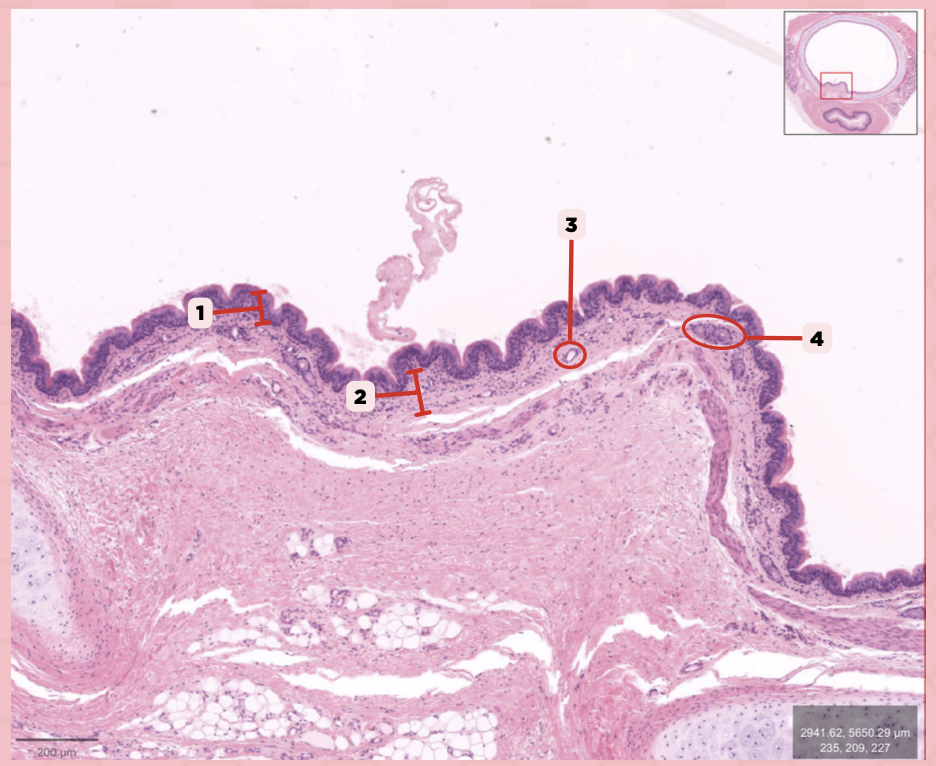

Identify the structure labeled as 1.

Nasal septum

Identify the structure labeled as 2.

Nasal cavity

Identify the structure labeled as 3.

Hard palate

Identify the structure labeled as 4.

Mucosal Associated Lymphoid Tissue (MALT)

What time of lymphocyte is numerous in the nasal cavity?

Keratinized stratified squamous epithelium

What’s the lining epithelium at #3?

No

Are Glands present at #1?

Lamina Propria

Identify the structure labeled as 1.

Adipocytes

Identify the structure labeled as 2.

Keratinized stratified squamous epithelium

Identify the structure labeled as 3.